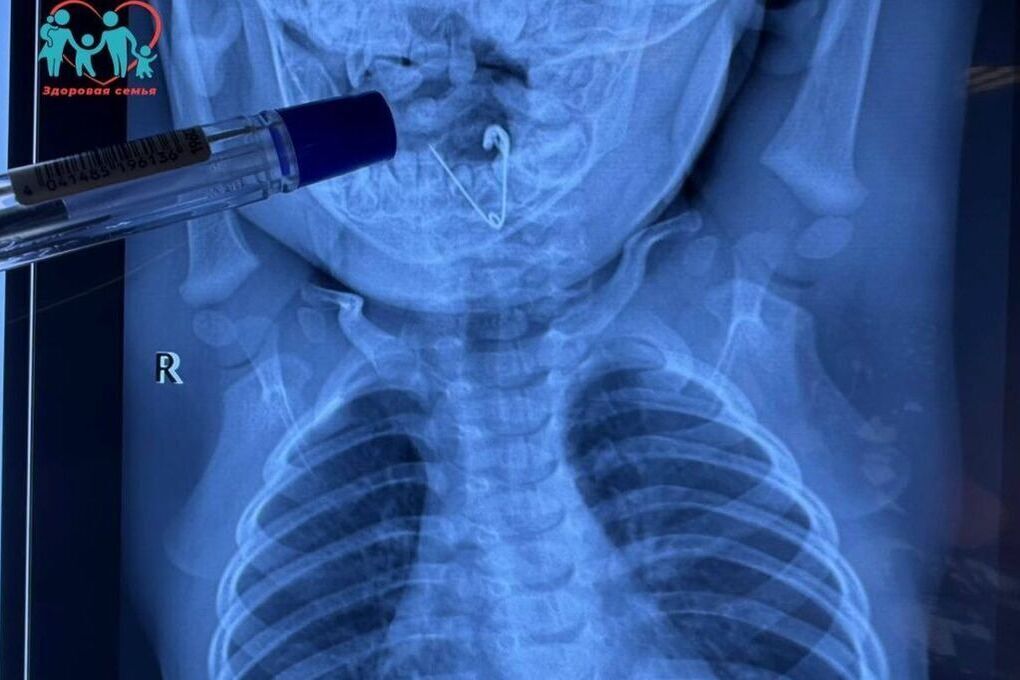

Ребенок съел вату

Ребенок съел вату 105 фото